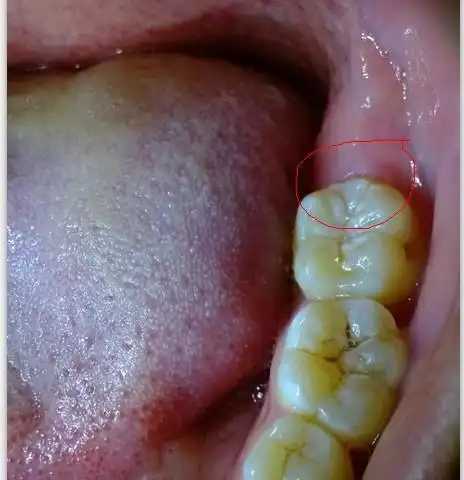

智齿在哪里最外面的牙横着在肉里

智齿的解剖学正规名称为"第三磨牙",因在人的智力发育旺盛时期(平均为

出现这6个症状的智齿!必须拔,不能留了

智齿破坏前牙的示意图